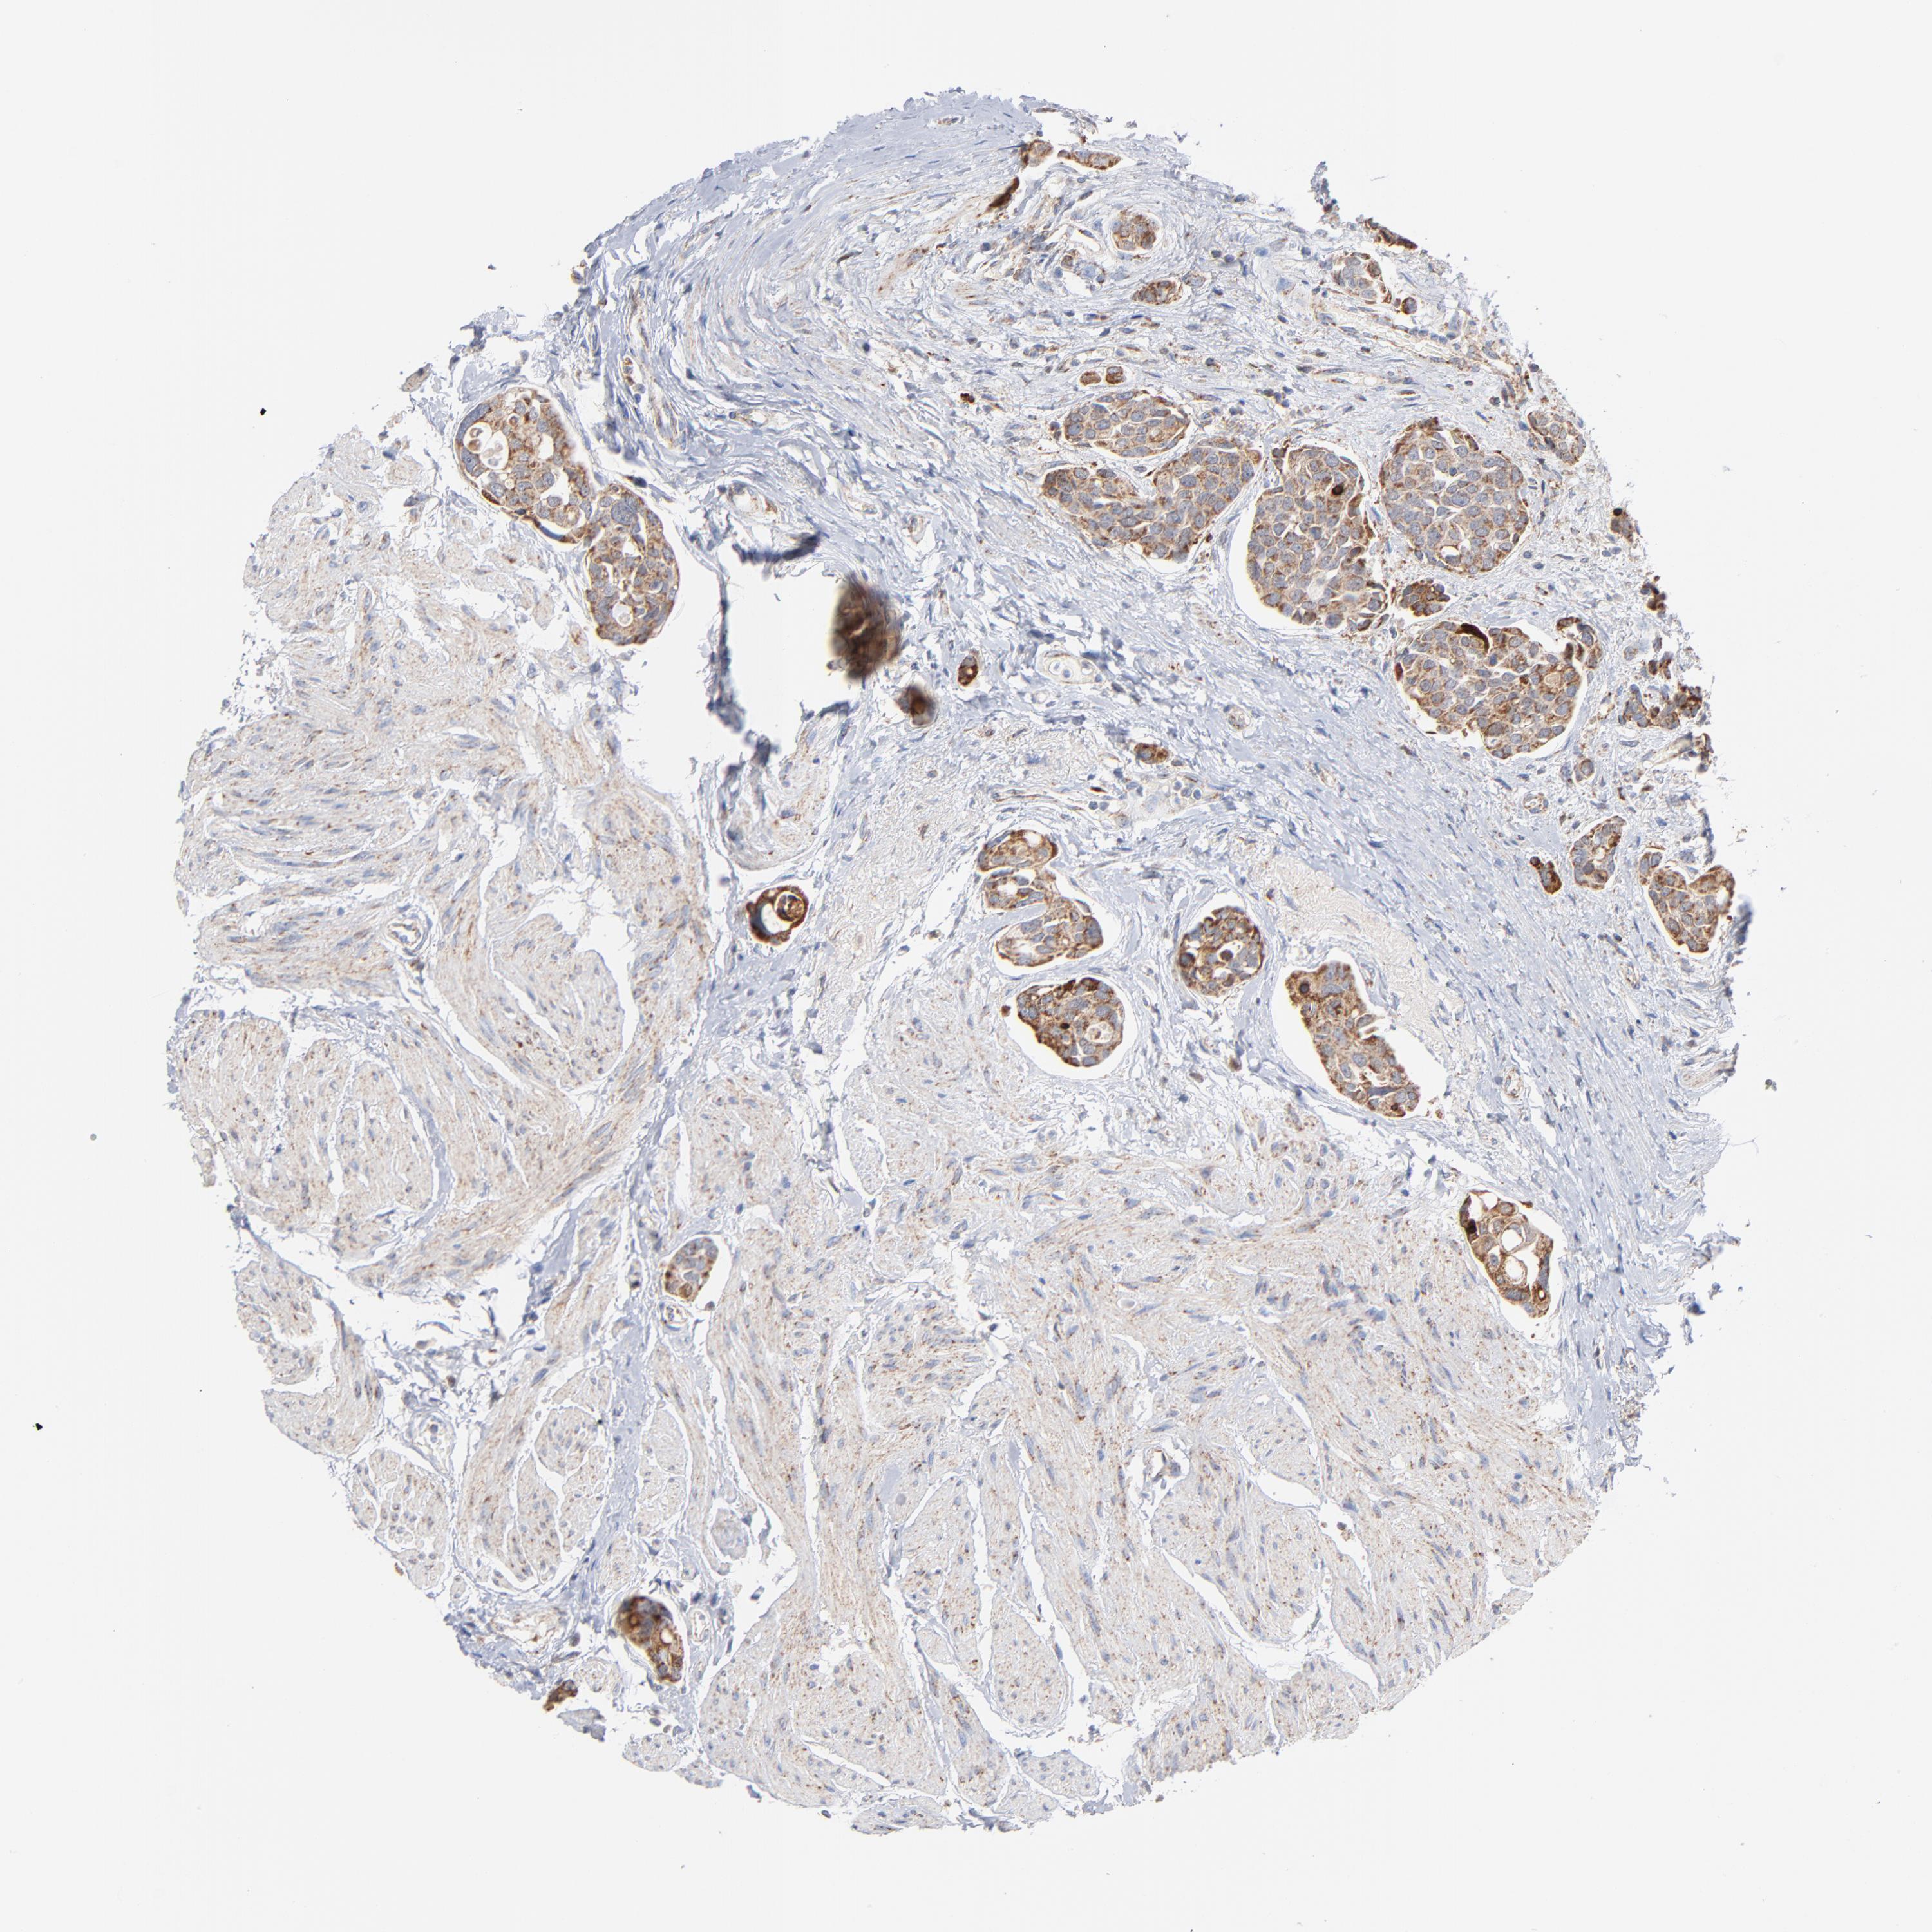

UROTHELIAL CANCER - Protein expressioni

A mouse-over function shows sample information and annotation data. Click on an image to view it in a full screen mode. Samples can be filtered based on level of antibody staining by selecting one or several of the following categories: high, medium, low and not detected. The assay and annotation is described here.

Antibody stainingi

Antibody staining in the annotated cell types in the current human tissue is reported as not detected, low, medium, or high, based on conventional immunohistochemistry profiling in selected tissues. This score is based on the combination of the staining intensity and fraction of stained cells.

Each image is clickable and will lead to virtual microscopy that enables deeper exploration of all samples and also displays staining intensity scores, fraction scores and subcellular localization as well as patient and tissue information for each sample.

Antibody HPA001825

Antibody CAB003857

Urothelial carcinoma, Low grade